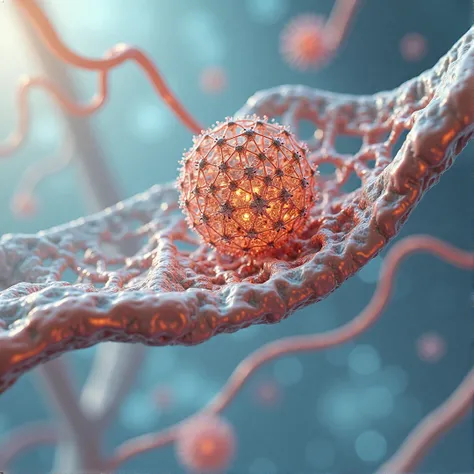

Pluripotent Hematopoietic Progenitor Cell

Pluripotent Hematopoietic Progenitor Cell

Pluripotent Hematopoietic Progenitor Cell

cell